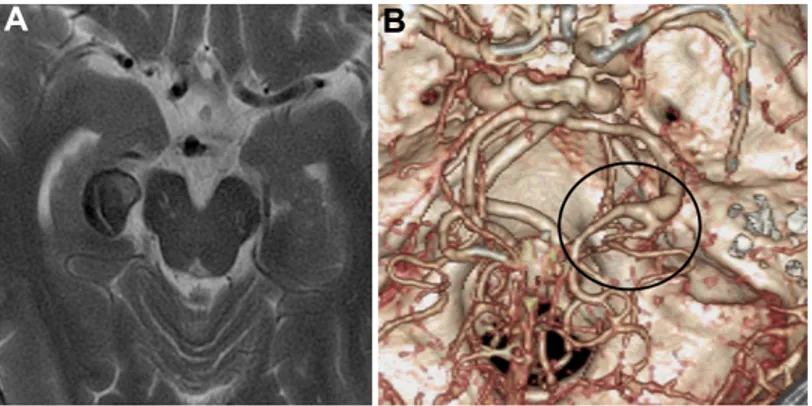

43岁的尹先生在一次常规体检过程中意外发现:其右侧大脑后动脉P2段存在一个梭形动脉瘤,且瘤体内部已伴有血栓形成。

然而尹先生当前的情况并非简单的动脉瘤切除手术,其治疗难度显著高于普通囊状动脉瘤。他所患的是右侧大脑后动脉P2段梭形动脉瘤,此类动脉瘤形态呈现不规则特征,瘤体伴随血栓形成,位置处于颅内关键血管区域,周围密集分布神经组织与重要血管分支,直接实施切除手术极易引发术中脑缺血,损伤神经功能,常规介入栓塞治疗也难以实现完全闭塞,手术方案的制定不容许存在任何差错。

为最大程度保障手术安全性,尹先生特意选择了INC国际脑血管手术专家川岛明次教授担任主刀医师。针对其具体病情,教授团队量身定制了精细化手术方案:右侧颞下入路联合STA-P3旁路手术及动脉瘤孤立术,每个操作步骤均精确至毫米级别,全方位规避手术相关风险。

手术实施过程中,专家团队首先通过精准的颞下入路,直达颅内动脉瘤所在位置,避开重要神经与血管分支;随后完成STA-P3血管搭桥,重建颅内远端血液供应,从根源上避免术中及术后脑缺血的发生;再通过动脉瘤孤立术,彻底将病变的动脉瘤与正常脑血管进行隔绝,阻止血流冲击引发破裂。

术中通过吲哚菁绿荧光血管造影反复确认,搭桥血管、P3段及PTA血管保持全程通畅,血液供应正常;随后打开动脉瘤,确认瘤体实现完全闭塞,同时完成血栓切除术,清理瘤体内陈旧血栓。整场手术全程保持精准操作,完美避开颅内关键功能区,未损伤任何神经功能。